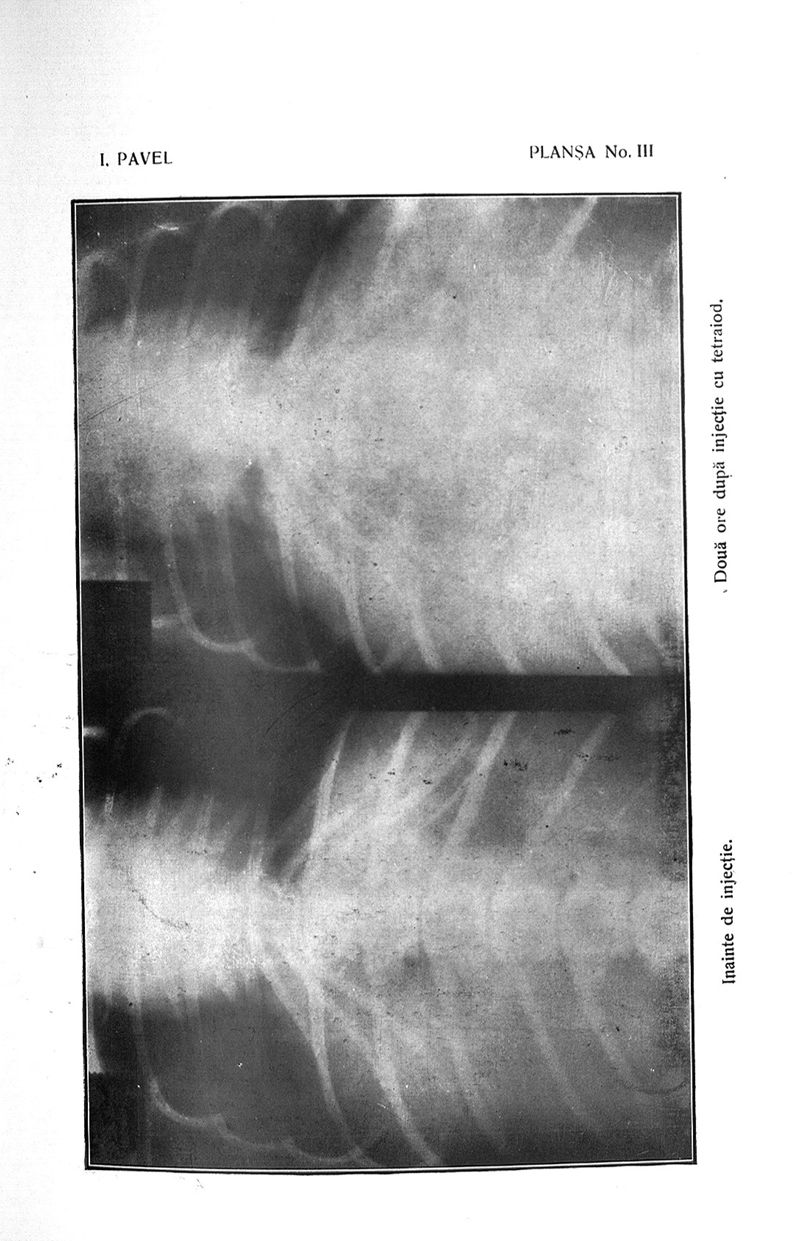

Pavel, I..

Titluri si lucrari stiintifice

Bucuresti, cartea romaneasca, 1930.